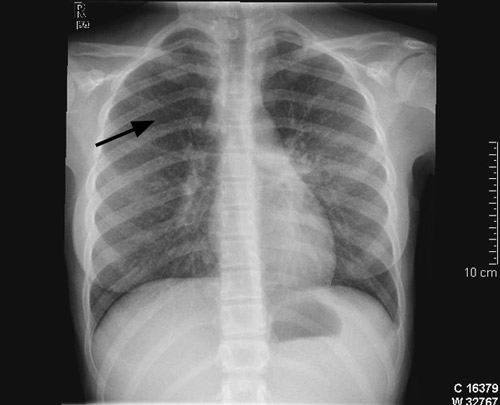

Ei veke etter innlegging var jenta klinisk dårlegare. Ho var kvalm og hadde svært redusert matlyst. Vi starta difor med intravenøs væsketilførsel og ernæring. Det vart tatt indusert sputum og gastrisk aspirat til direkte mikroskopi, PCR og dyrking med tanke på Mycobacterium tuberculosis. Vi rekvirerte også ein Quantiferon-TB Gold test. Dagen etter vart ho spinalpunktert, og vi fann leukocyttar 444 · 10⁶/l (< 3,0 · 10⁶/l), 80 % polynukleære og 20 % mononukleære, glukose 3,2 mmol/l og protein 0,31 g/l (< 0,50 g/l). På mistanke om miliær tuberkulose med meningitt starta vi med standard antituberkuløs behandling med isoniazid, rifampicin, pyrazinamid og etambutol samt pyridoksin. Dagen etter vart det i tillegg starta med intravenøs cefotaksimbehandling. Tre dagar seinare vart det gjort MR av cerebrum, som viste multiple små kontrastladande lesjonar i hjerneparenkymet, dei fleste i overgangen mellom grå og kvit substans, og i tillegg ein lesjon i basalgangliene på venstre side (fig 3a). Det var minst 16 lesjonar supratentorialt og tre infratentorialt, og den største målte 5 mm i diameter. Det vart gjort ekkokardiografi som viste normale forhold. Det vart ikkje påvist antistoff mot humant immunsviktvirus (hiv).

På grunn av usikker diagnose og komplisert sjukdom vart barnet dagen etter MR-undersøkinga overført til eit anna universitetssjukehus. Vi fekk så svar på Quantiferon-TB Gold som var 5,17 IU/ml (< 0,35 IU/ml). Augelege fann at jenta hadde korioretinale infiltrat bilateralt. MR av abdomen med kontrast viste hepatosplenomegali utan fokal patologi samt forstørra lymfeknutar i leverhilus og paraaortalt. 13 dagar etter overføring kom det melding om positiv polymerasekjedereaksjonstest (PCR) for M tuberculosis-komplekset i indusert sputum. Ei veke seinare vart det stadfesta vekst av M tuberculosis i indusert sputum og i spinalvæske. Stammen var sensitiv for alle testa medikament. Etter 14 dagar vart jenta overført til lokalsjukehuset. Røntgen av thorax etter to månaders behandling viste markert tilbakegang av lungefortettingane. Samstundes vart det tatt ein kontroll-MR av cerebrum som viste at dei intracerebrale lesjonane hadde auka i storleik og at det var fleire nytilkomne lesjonar (fig 3b). Jenta var framleis innlagt i avdelinga. Ho hadde ingen nyoppståtte nevrologiske symptom eller utfall. Visuelt framkalte potensial (VEP), som er ein spesifikk test av nervus opticus, vart undersøkt tidleg i behandlingsforløpet og etter åtte veker. Funna ved desse undersøkingane var normale.

Ved kliniske kontrollar to, åtte og tolv månader etter utskriving var det tilfredsstillande forhold. MR av cerebrum etter sju månader med behandling viste nær komplett tilbakegang av alle lesjonar. Dei korioretinale infiltrata gjekk også fullstendig tilbake. Lymfocyttpopulasjonar vart kontrollert på same tidspunkt og viste no tilnærma normale verdiar.